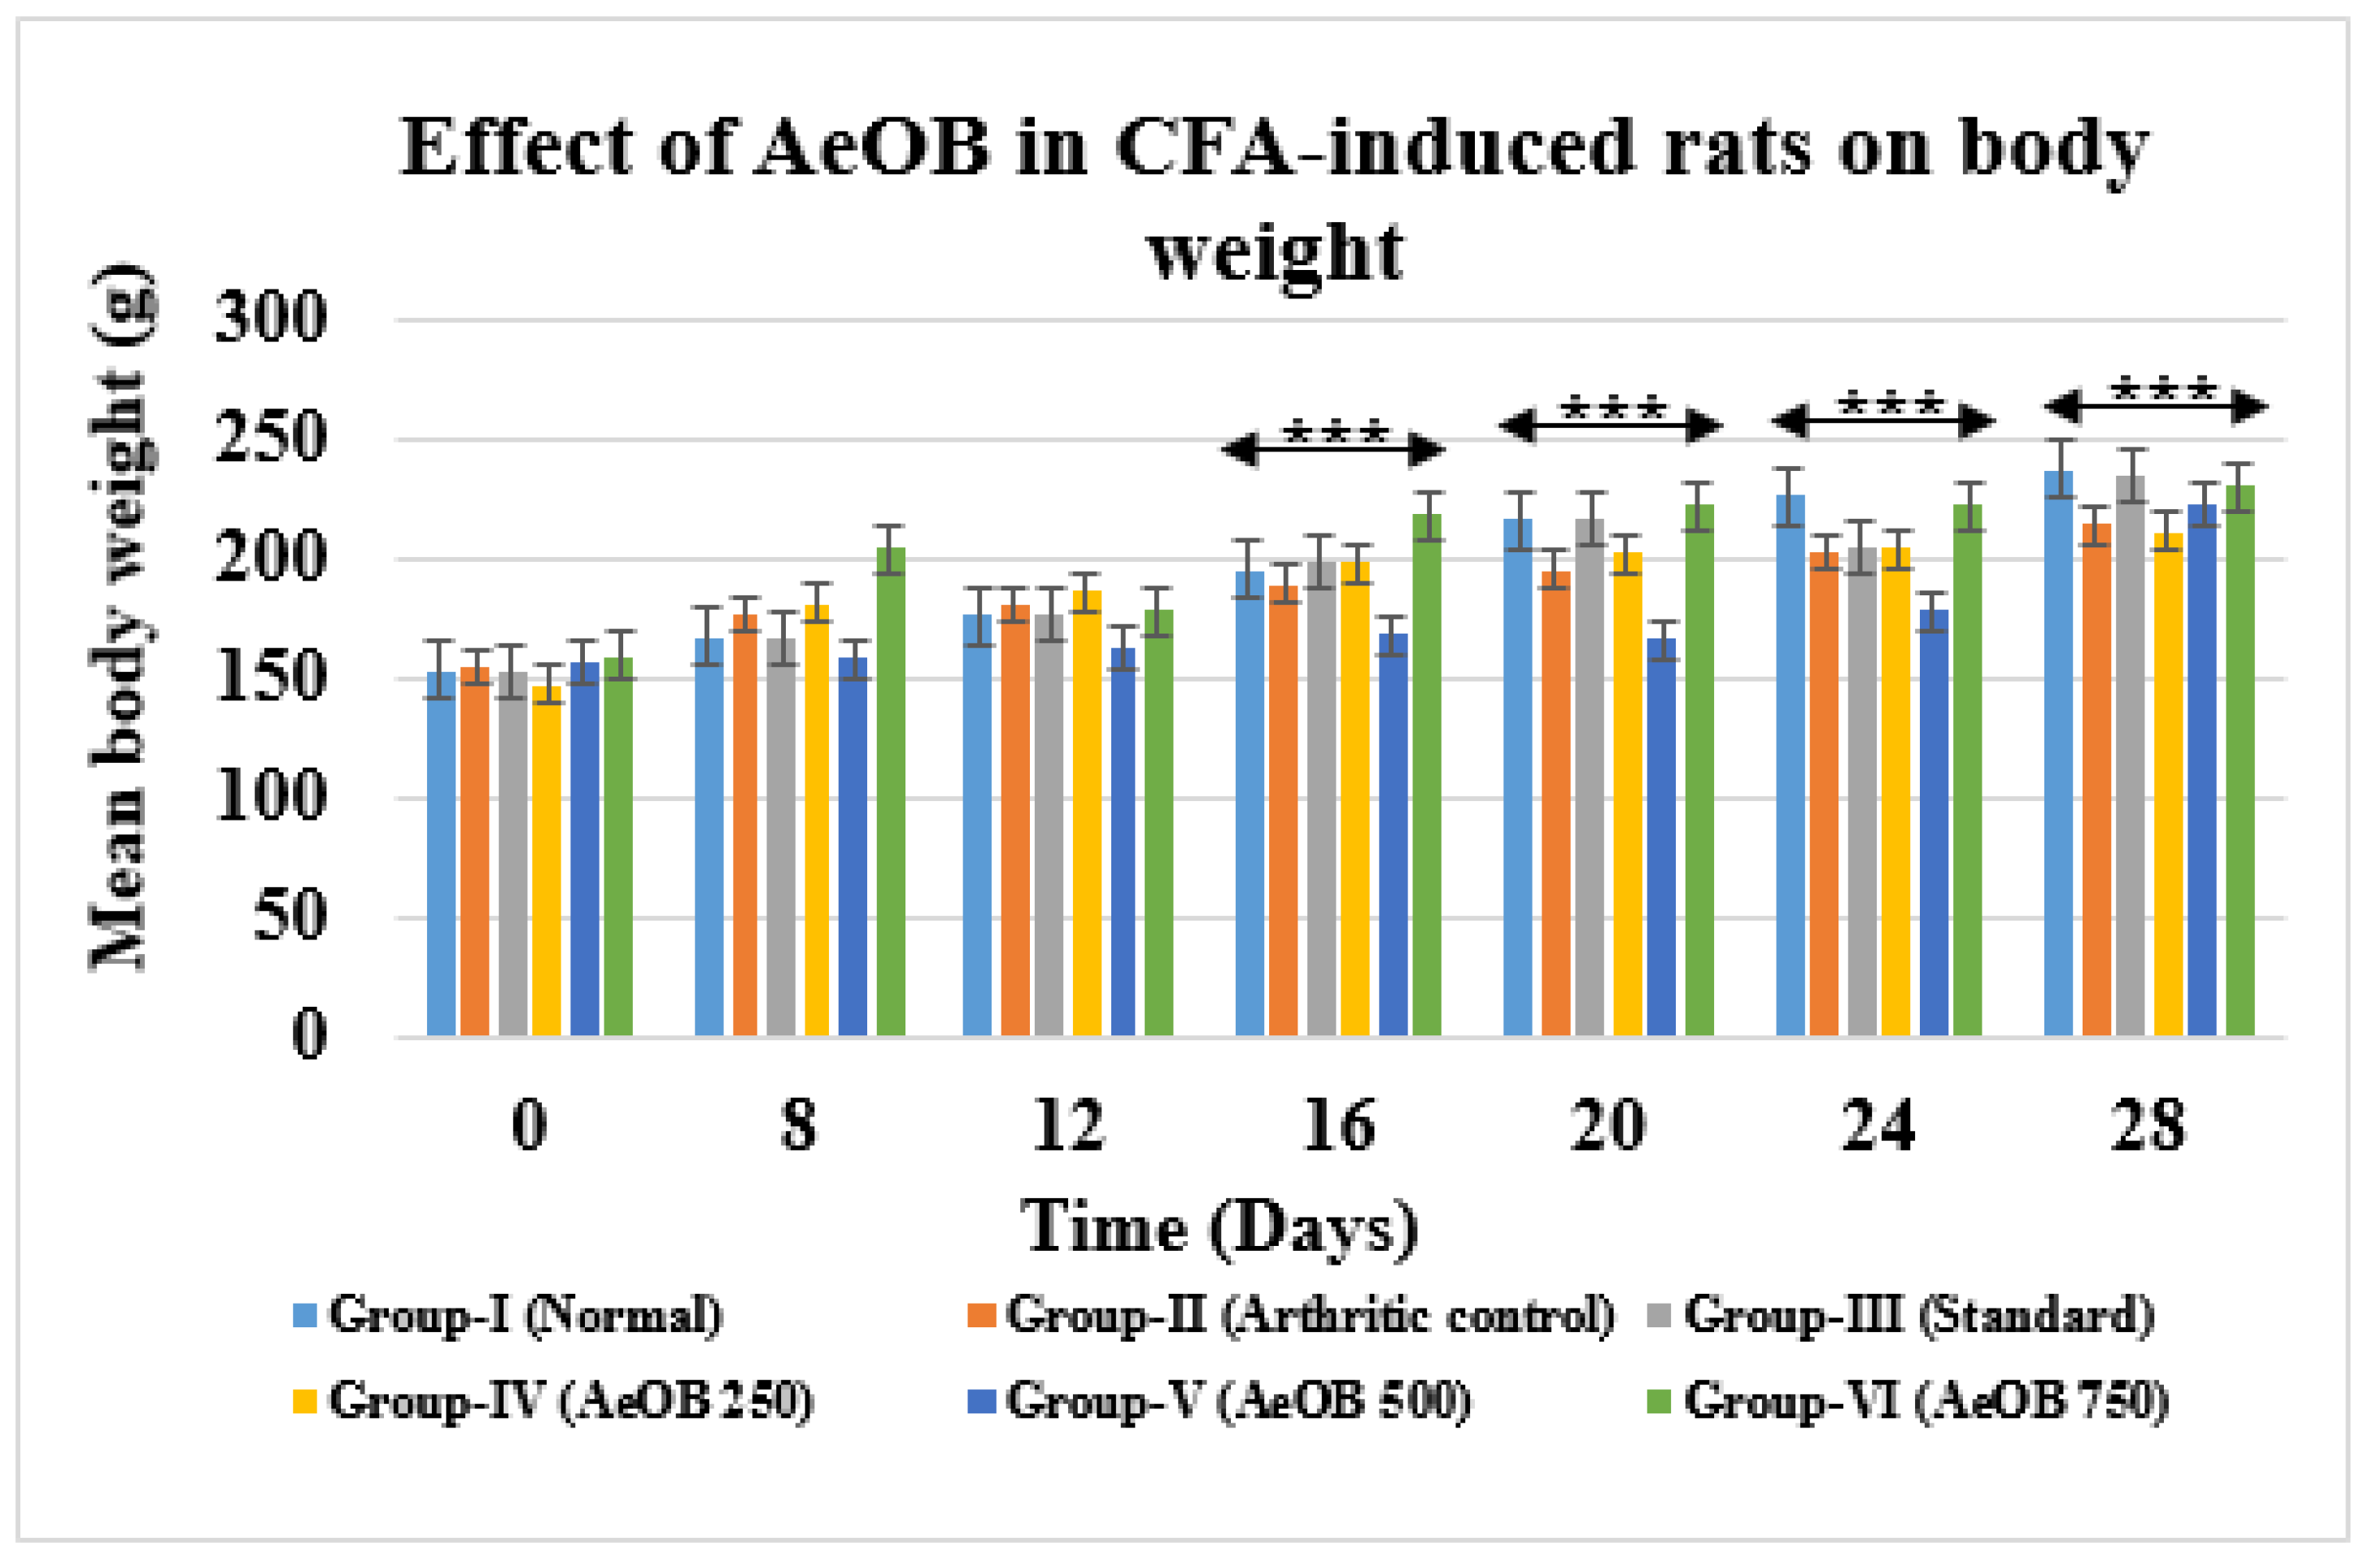

2.6.4. Body Weight

4.7.9. Body Weight Measurements